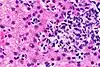

.png.webp) |

B Cell | Lymphocyte | B Cell |

|

8-10 |

|

[14][4] |

|

Plasma Cell | Lymphocyte | B Cell |

|

8-10 |

|

[4][15] |

|

Memory B Cell | Lymphocyte | B Cell |

|

8-10 |

|

[4][16] |